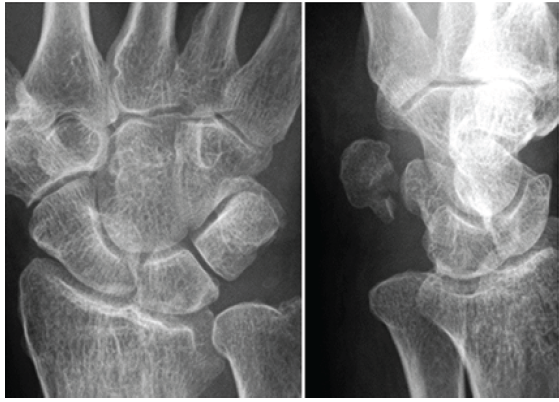

A 64-year-old right-handed woman presented with the sudden onset of severe right wrist pain sustained after a fall. Physical examination demonstrated swelling and tenderness along the ulnar aspect of the volar wrist. Plain radiographs and computed tomography (CT) scans revealed a comminuted intra-articular pisiform fracture featuring a small proximal fragment and articular incongruity with a cortical gap and a step-off (Fig. 1 and 2).

Figure 1: Initial plain radiographs demonstrate an isolated displaced intra-articular pisiform fracture with pisotriquetral joint incongruity.